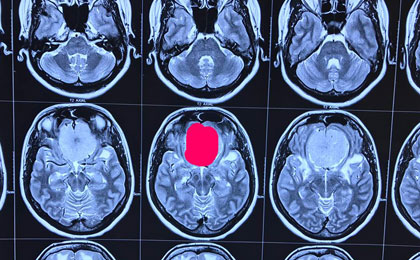

Brain Tumor Surgery  14/02/2019

frontal epidermoid pre t2w

• frontal epidermoid pre t2w

frontal epidermoid pre diffusion

• frontal epidermoid pre diffusion